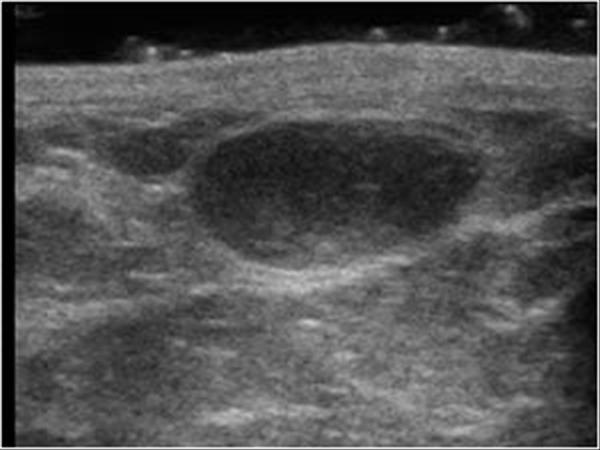

Hoại tử mỡ tuyến vú

» Thông tin: Nữ giới – 54 tuổi.

» Lâm sàng: Khối tuyến vú / Sau phẫu thuật u vú.